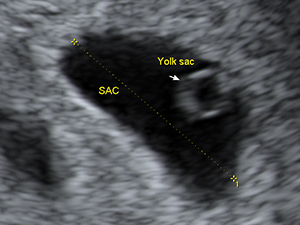

First Trimester

Gestational sac and yolk sac at 6 weeks